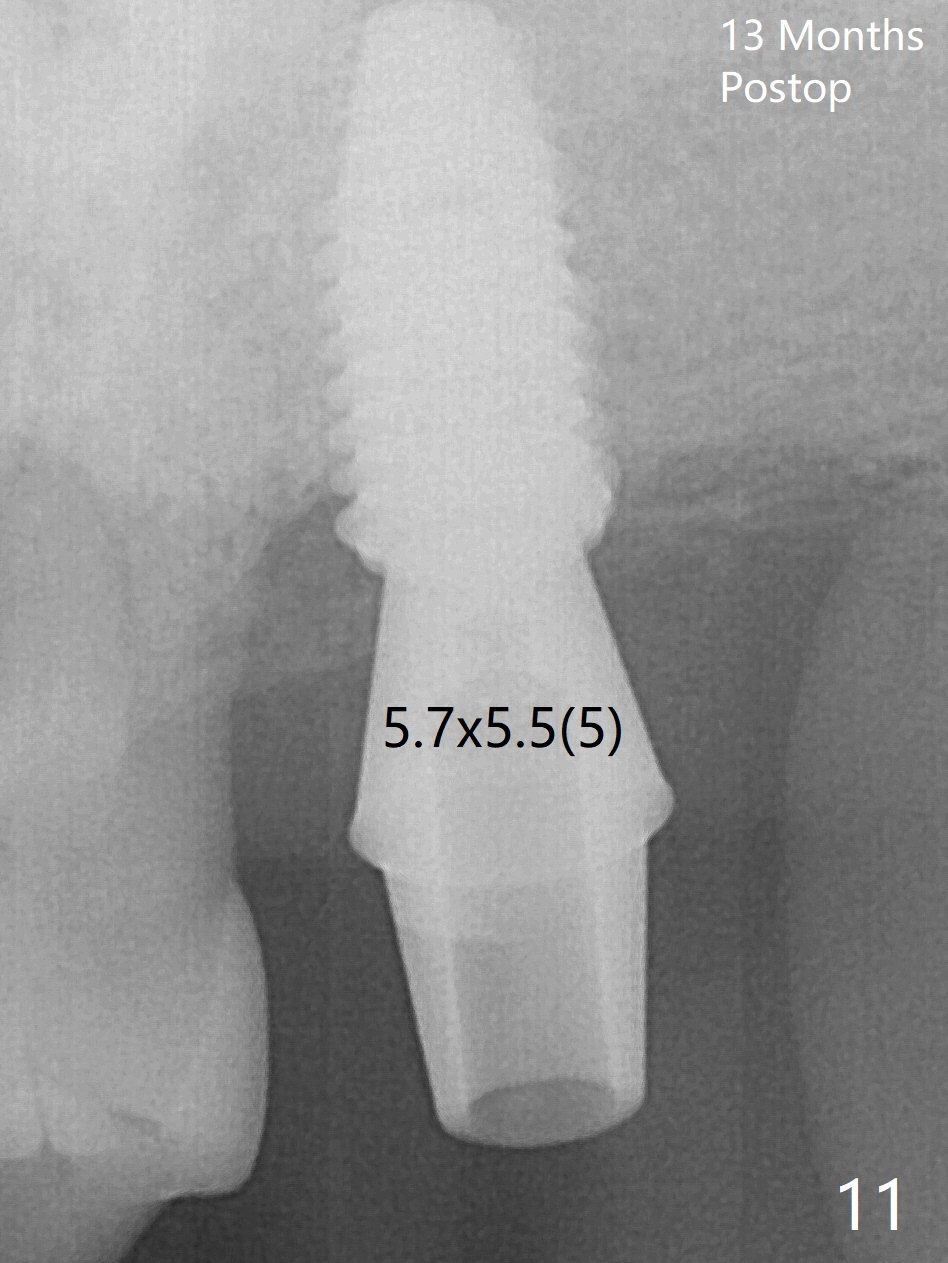

Although the buccal (Fig.1 (mesial view of the extracted tooth #15): B) root is larger than the palatal (P) one, the palatal socket is larger than the buccal one (Fig.2 white area) because of the bone loss of the former. For better restoration, osteotomy (Fig.2 red line) is initiated in the buccal slope of the septum (S) so that the final osteotomy is in the middle of the whole socket (Fig.3 red box). In fact a 3 mm stopper is not used because of the slope and the clumsy stopper. Stopper would be indicated if the bottom of the bone were flat. At first a 4x10 mm dummy implant is placed with stability (Fig.4). After further osteotomy and sinus lift (Fig.6 red dashed line: sinus floor), a 5x10 mm implant is placed with 30 Ncm, followed by insertion of a 5.2x8(2) mm temporary abutment (Fig.5,6). The latter holds an immediate provisional and Vanilla Graft/Osteogen (Fig.7 *) in place (^: distal crestal bone). Although the bone looks normal around the implant 7.5 months postop (Fig.4), the implant is unstable, probably due to the large preexisting defect. In contrast the implant placed at the healed site of #3 is stable 6.5 months postop. The 8x5 mm healing abutment that dislodged for 1 day could not return. A 6x5 mm one is used; it appears that the bone density mesial and distal to the implant is low (Fig.9 *). The implant looks normal and is stable 13 months postop (Fig.10). A 5.7x5.5(5) mm cementation abutment is placed for a provisional (progressive loading, Fig.11). There is no pain associated with the provisional for mastication. Impression is taken 7 days later. The patient has pain when the permanent crown is cemented. It appears that the implant does not osteointegrate and should be removed. A 6x14 mm tissue-level implant will be immediately placed following a 5 and 6x14 mm taps and bone graft and PRF (Metronidazole). In fact there is no pain when the existing abutment is torqued at 35 Ncm 1 year 8 months postop (Fig.12). The mesiogingival portion of final restoration (Fig.13 arrowheads) should be bulky so that the gingival embrasure (red dashed line) is minimal to reduce food impaction.